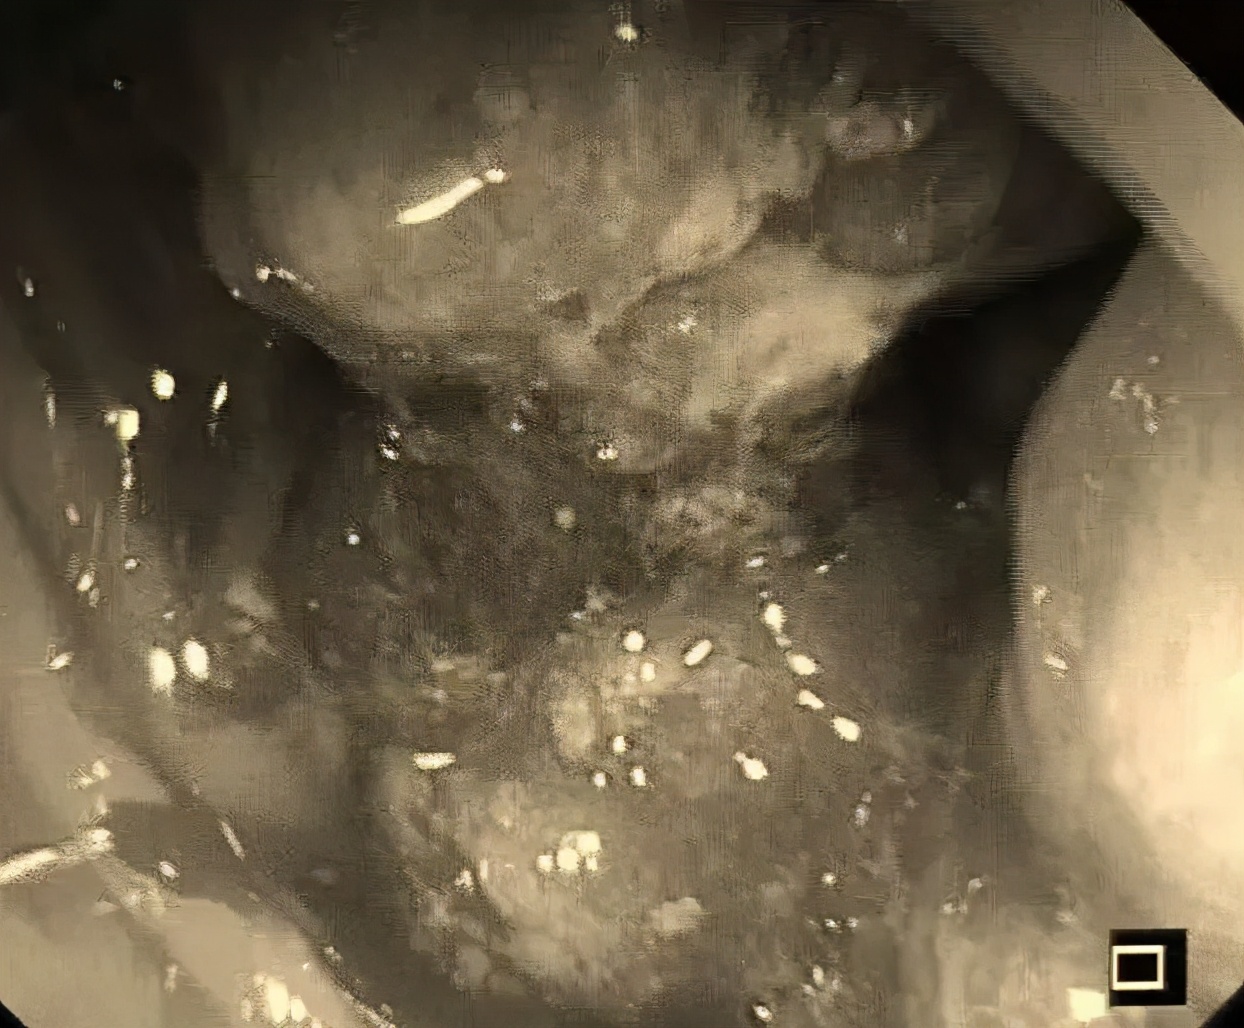

听完他的自诉,检查完他的体征,我心里不免警惕起来:“不会是又一个被痔疮耽误的病人吧?”尽管我心里但愿我的猜测是做错误的,但是,肠镜刚进去,就印证了我的猜测!

距肛门10-12cm处,一个巨大环周性占位!直肠癌,而且应该是晚期!

这是2019年来,我们科发现的第10个当成痔疮耽误的病人,平均一月一个!

巨大占位性病变

通过肠镜能直视结直肠内部,观察肿块的形态,上下缘及距肛门缘的距离,同时可取病理送检,确定肿块性质及分化程度。